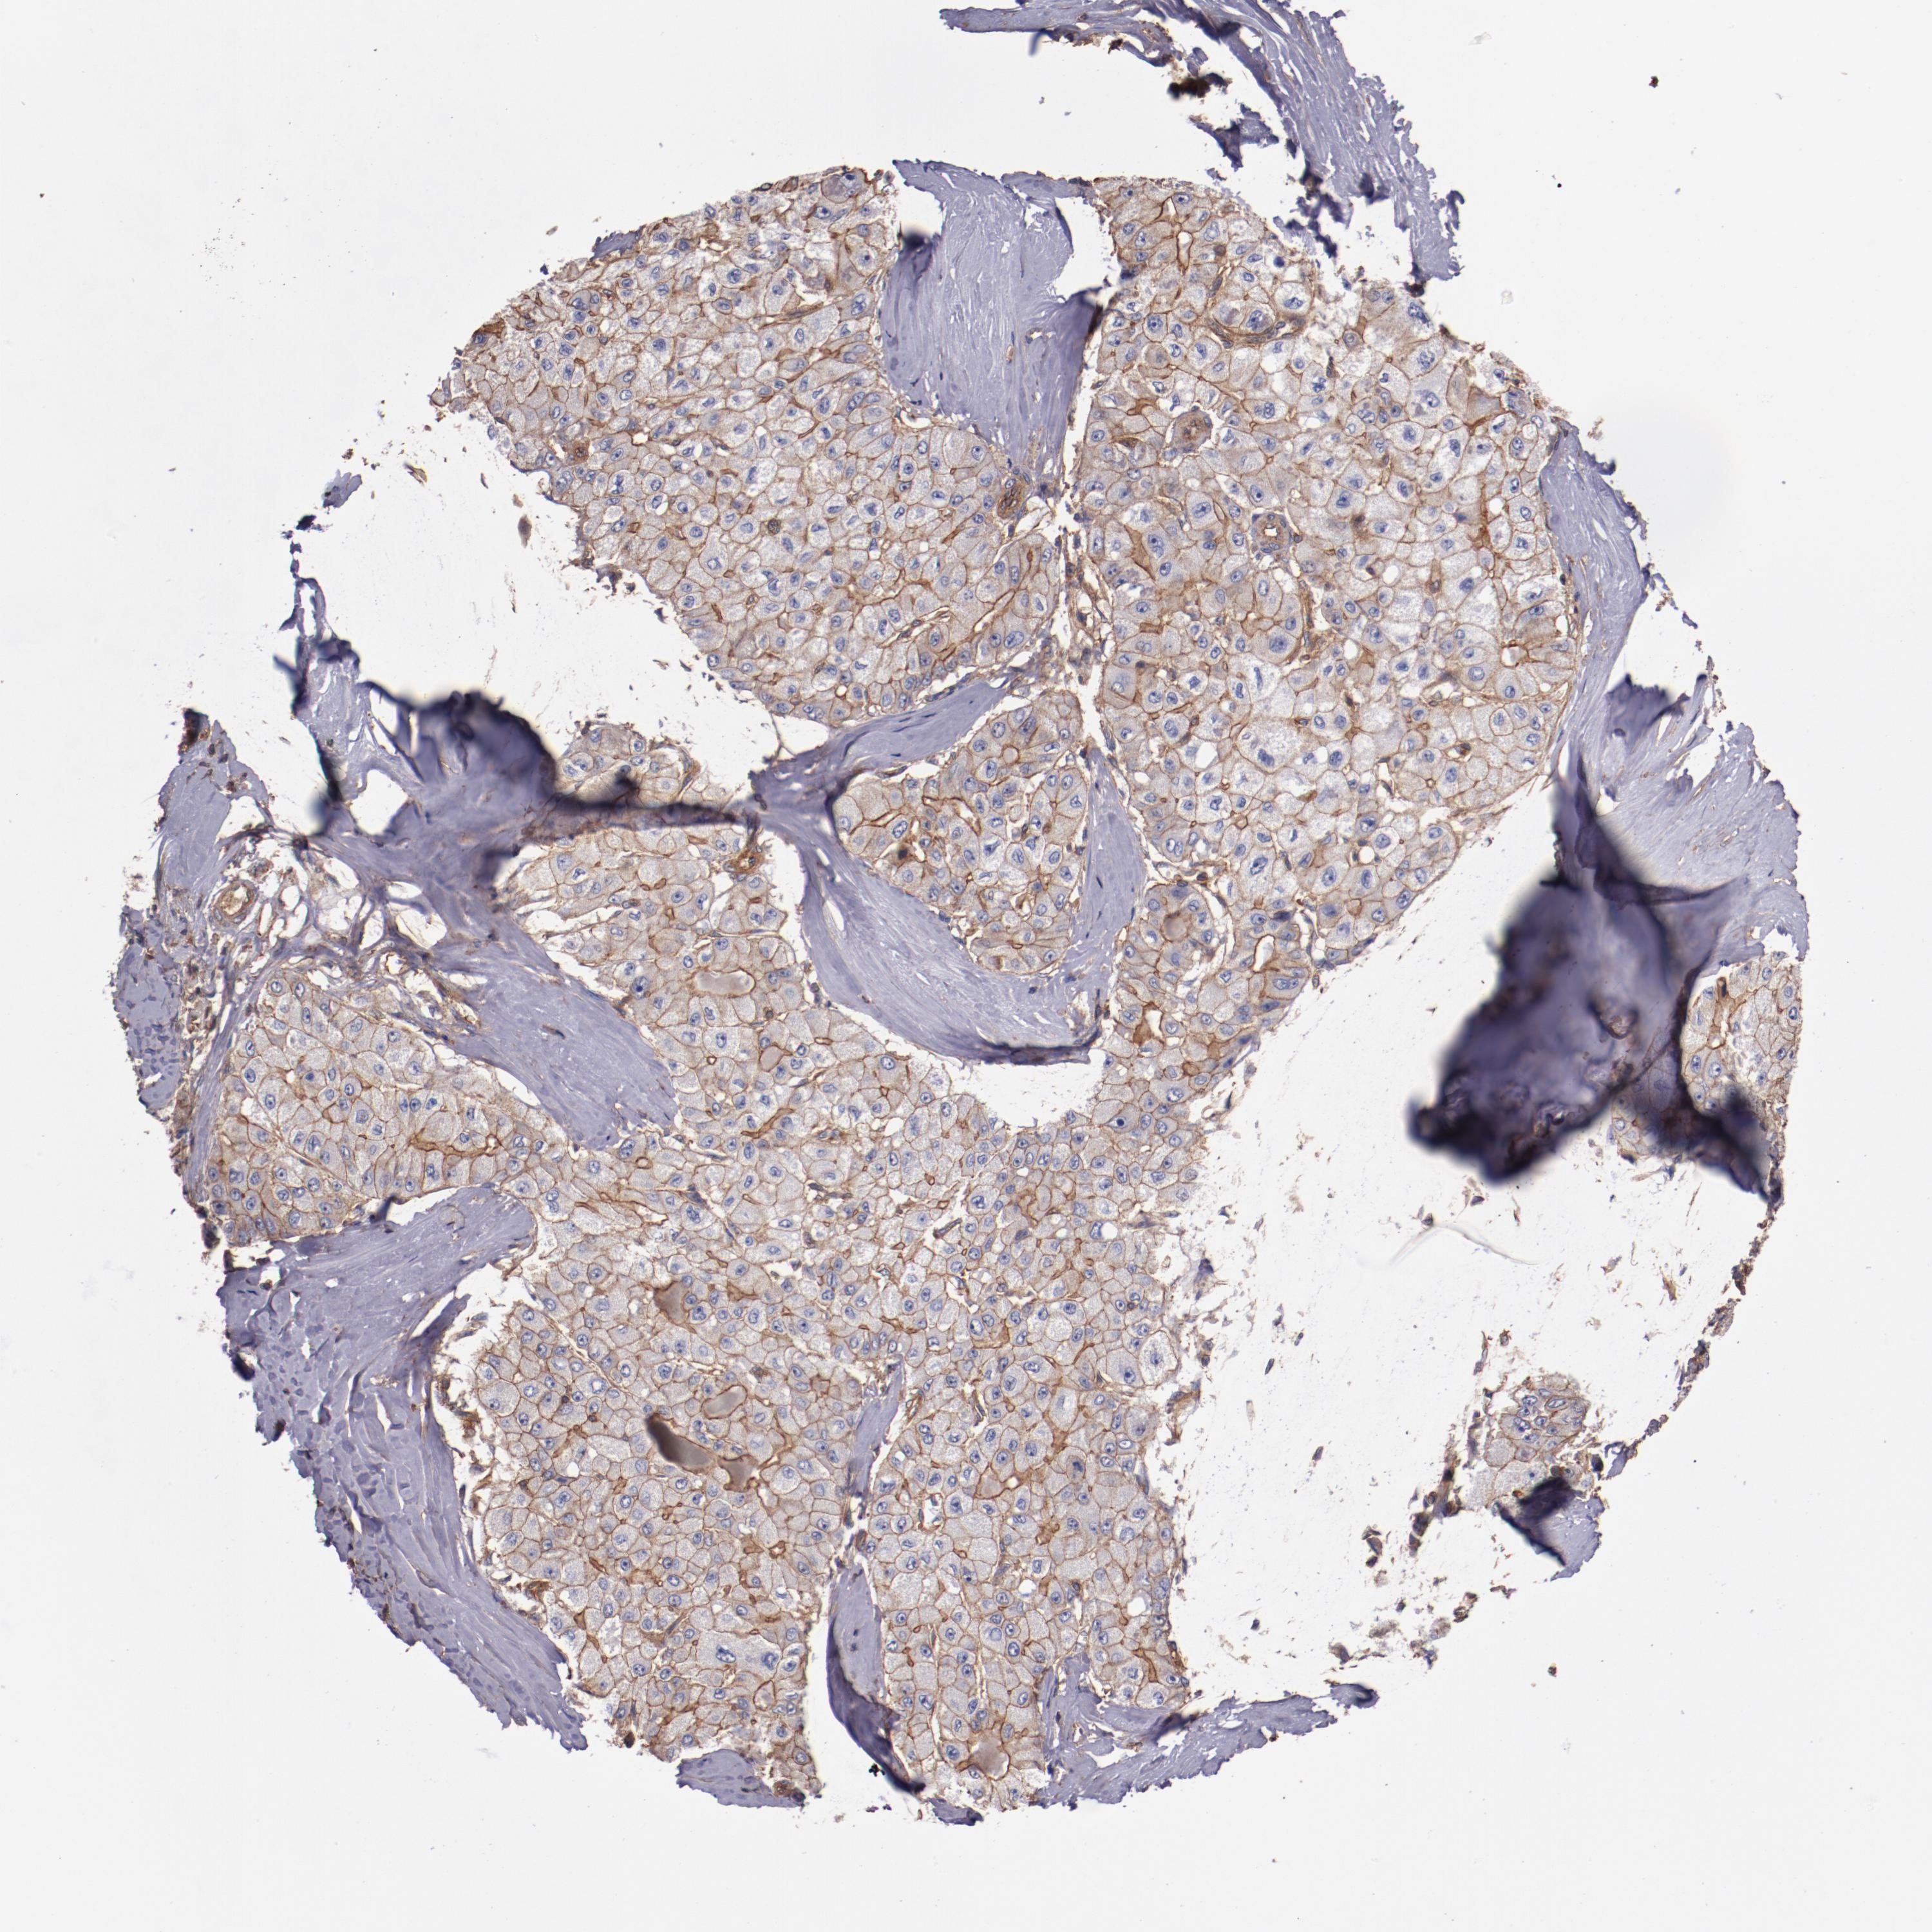

LIVER CANCER - Protein expressioni

A mouse-over function shows sample information and annotation data. Click on an image to view it in a full screen mode. Samples can be filtered based on level of antibody staining by selecting one or several of the following categories: high, medium, low and not detected. The assay and annotation is described here.

Note that samples used for immunohistochemistry by the Human Protein Atlas do not correspond to samples in the TCGA dataset.

Antibody stainingi

Antibody staining in the annotated cell types in the current human tissue is reported as not detected, low, medium, or high, based on conventional immunohistochemistry profiling in selected tissues. This score is based on the combination of the staining intensity and fraction of stained cells.

Each image is clickable and will lead to virtual microscopy that enables deeper exploration of all samples and also displays staining intensity scores, fraction scores and subcellular localization as well as patient and tissue information for each sample.

Antibody HPA001849

Staining

High

Medium

Low

Not detected

Intensity

Strong

Moderate

Weak

Negative

Quantity

>75%

75%-25%

<25%

None

Location

Nuclear

Cytoplasmic/membranous

Cytoplasmic/membranous,nuclear

Cholangiocarcinoma

Carcinoma, Hepatocellular, NOS